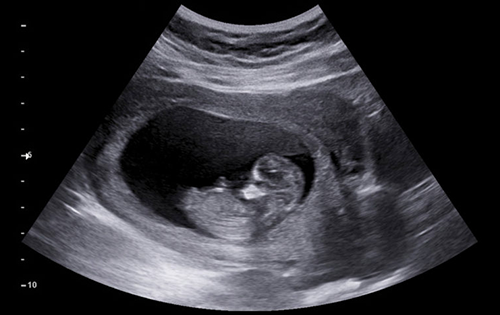

Advanced ultrasound, screening, and diagnostic services for accurate fetal and maternal health assessment.

During a fetal scan, your baby may be in any position—facing up, down, or turned sideways. Sometimes, we need to wait for the baby to move into an optimal position to assess all organs thoroughly. This is especially common during NT scans, anomaly scans, and fetal echocardiography, which can take longer than expected.

Performing the scan requires skill and concentration. So the doctor may be quiet for short periods of time which is entirely normal. After the initial test and measurements are complete, the baby will be shown to the expecting parents and explained.